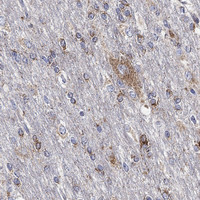

Immunohistochemistry analysis in human cerebral cortex and tonsil tissues using Anti-SCCPDH antibody. Corresponding SCCPDH RNA-seq data are presented for the same tissues.